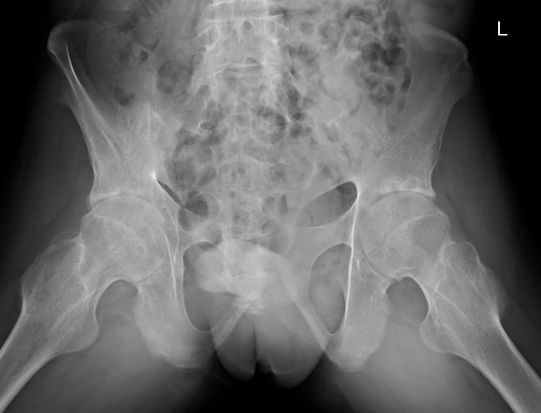

图:强直性脊柱炎伴轻度髋关节结构破坏改变

例1:21岁男性,AS患者,双髋关节疼痛伴活动受限4年